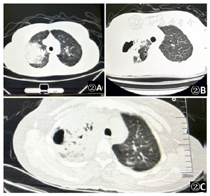

2020年9月21日肺CT(图2A):双肺炎症,右上叶为主。2020年9月28胸部CT(图2B):双肺炎症,右肺上叶为主(范围较前扩大),密度增高,右肺上叶病灶内多发空腔形成。2020年10月14胸部CT(图2C):双侧肺炎范围较前缩小,右肺上叶为主。

2020年9月21日肺CT(图2A):双肺炎症,右上叶为主,给予哌拉西林联合莫西沙星,辅以补液、降温治疗。初始治疗评估:2020年9月25体温从39.2℃~40.4℃之间降至38.0℃~38.9℃之间,SPO2 88%~92%(储氧面罩5 L/min),R 24~30次/min,BP正常,但患者咳嗽、咳痰加重,咳黄色黏痰,无力咳出。药敏结果:血培养示铜绿假单胞菌,对亚胺培南/哌拉西林/左氧氟沙星/庆大霉素敏感。痰培养:铜绿假单胞菌,对亚胺培南/头孢哌酮/左氧氟沙星/庆大霉素敏感,故依据药敏结果调整抗生素为亚胺培南联合左氧氟沙星[3]。2020年9月27患者咳嗽咳痰症状有好转,咳白色黏痰,不易咳,胸闷、气短症状稍有好转,调整抗生素为亚胺培南联合莫西沙星[3]。2020年9月28胸部CT(图2B):双肺炎症,右肺上叶为主(范围较前扩大),密度增高,右肺上叶病灶内多发空腔形成。患者情况:患者咳痰无力,进行床旁支气管镜检查。2020年10月5日患者T 36.8℃~37.4℃,SPO2 91%~95%(鼻导管吸氧2 L/min),患者咳嗽、咳痰症状缓解,量多易咳出,稍感气短、精神可。给予头孢哌酮舒巴坦联合左氧氟沙星降阶梯抗生素治疗[3]。2020年10月14胸部CT(图2C):双侧肺炎范围较前缩小,右肺上叶为主。心脏彩超无明显变化。病情情况:体温正常,偶有咳嗽、咳痰。好转出院。